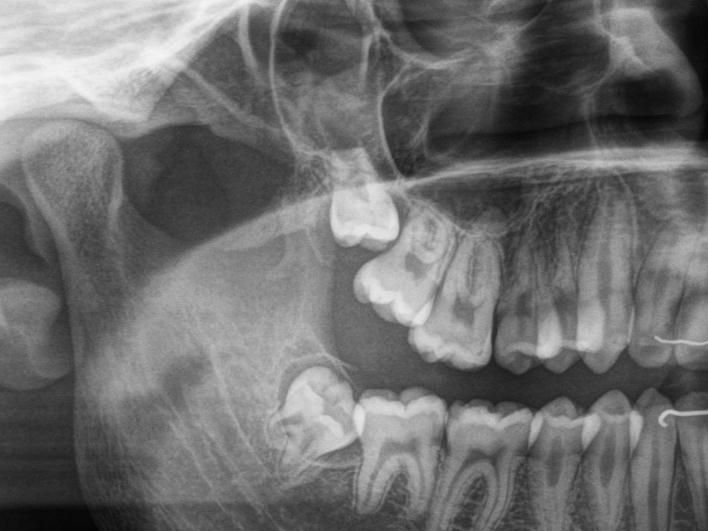

Klinische und radiologische Diagnostik der Zähne, des Parodonts und der Funktion.

Diagnostik